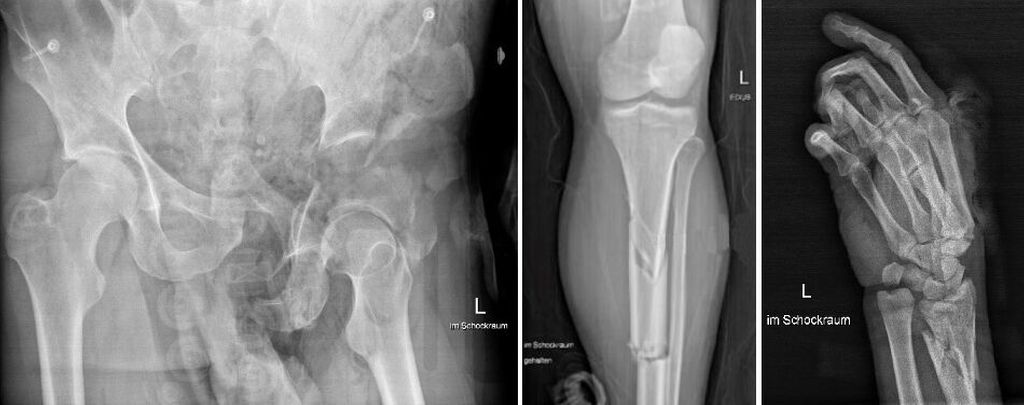

Das Schockraum-ABCDE wird durchgegangen. Im eFAST zeigt sich primär keine freie intraabdominelle Flüssigkeit. Ein Thorax- und ein Beckenröntgen werden angefertigt. Der T-POD wird belassen. Es ist von einem großen darunterliegenden Weichteiltrauma auszugehen. Aufgrund der limitierten Venensituation und des Vorliegens einer Zentralisation muss ein zentraler Venenkatheter angelegt werden. Das Schockraumteam entschließt sich, über die rechte A.femoralis eine REBOA-Schleuse einzubringen, während zeitgleich Röntgenbilder von Unterschenkel und Hand angefertigt werden (Abb.2) und mit dem Massentransfusionsprotokoll begonnen wird (6 Erythrozytenkonzentrate, 1800 PPSB, 4g Fibrinogen, 1g Tranexamsäure). An der linken unteren Extremität zeigt sich eine offene, in einer Vakuumschiene versorgte Unterschenkelfraktur und im Bereich des distalen Unterarms eine drittgradig offene Fraktur mit exzessivem Weichteilschaden, bis in die Mittelhand reichend. Erste ausgewählte Laborparameter sind in Tabelle 1 ersichtlich.

Nach einer Schockraumzeit von 35 Minuten kann das Polytrauma-CT durchgeführt werden. Hier zeigen sich folgende weitere Verletzungen: Scapulafraktur links, Serienrippenfrakturen 1–8links und 1–4 rechts, Leberlazeration, Milzlazeration mit nun schon sichtbarer freier Flüssigkeit, komplexe Acetabulum-/Ileumtrümmerfraktur links mit Abbruch der Kontrastierung der A. iliaca communis mit großem Hämatom und aktivem Kontrastmittelextravasat.

Da der Patient im CT zunehmend instabiler wird (RR-Werte um die 70mmHg systolisch trotz hochdosierter Arterenol-Gabe), wird um 16:50 Uhr ein REBOA-Katheter ohne Bildgebung in die Zone III eingebracht. In Folge stabilisieren sich die RR-Werte relativ rasch auf bis über 120mmHg, sodass der Patient in den Hybrid-OP transferiert werden kann. Nach Entfernung des T-POD zeigt sich eine ausgedehnte Weichteilverletzung mit offenliegender Darmbeinschaufel links.